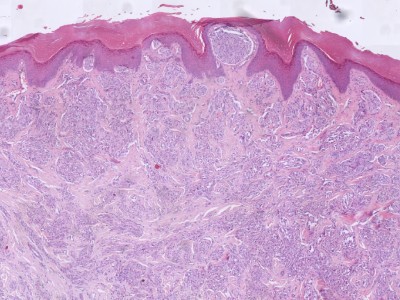

![Histologie STUMP (click on photo to enlarge) [source: Kevin Kwee / Afdeling Pathologie MUMC] Histologie STUMP](../../../pacoupes/thumbnails/STUMP-1.jpg) |

![Histologie STUMP (click on photo to enlarge) [source: Kevin Kwee / Afdeling Pathologie MUMC] Histologie STUMP](../../../pacoupes/thumbnails/STUMP-2.jpg) |

ingescande coupe (zoom) |